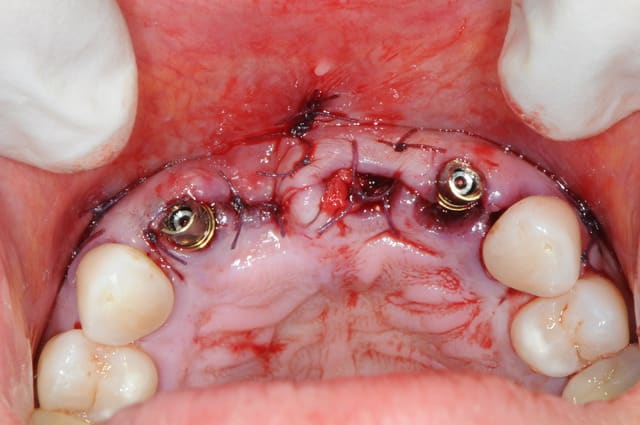

au mois d'octobre (j+5 mois), et malgré mon insistance, la patiente refusant de mettre en place les greffes muco-conjonctives pour récupérer le fiasco attendu sur 11, on débute la prothèse.

elle ne veut plus continuer, et sa reprise tabagique m'interdit une greffe. c'est vraiment dommage.

+ piliers et structure du bridge en zircone (j'adore mon proto)

+ piliers en place

+ mordu occlusale